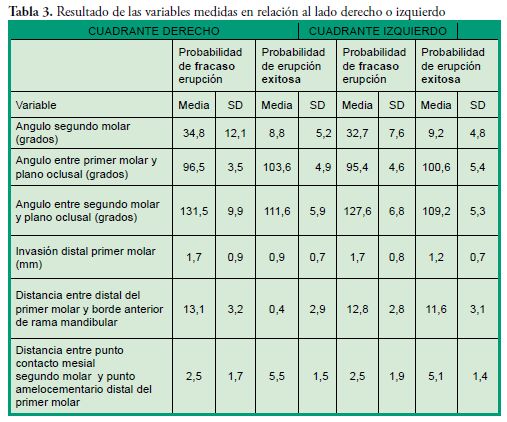

Los pacientes que presentaron probabilidad de fracaso en la erupción corresponden al 1,43% de la muestra, su edad promedio fue de 10 ± 1,7 años, en relación al sexo el 73,3% son mujeres. La variable que se utilizó para determinar la probabilidad de éxito o fracaso en la erupción fue el ángulo del segundo molar: -menor o igual a 24° se consideró probabilidad de erupción exitosa, mientras que -un ángulo de 25° o más se consideró con probabilidad de fracaso en la erupción de acuerdo al promedio manifestado por Evans en 1988 (promedio de 25° con un rango entre 15° a 65°). Las Tablas 1, 2 y 3 expresan los resultados de las variables indagadas y su relación con la probabilidad o no de erupción, la presentación en forma uni o bilateral y su distribución por cuadrante.

Los pacientes que presentaron probabilidad de fracaso en la erupción corresponden al 1,43% de la muestra, su edad promedio fue de 10 ± 1,7 años, en relación al sexo el 73,3% son mujeres. La variable que se utilizó para determinar la probabilidad de éxito o fracaso en la erupción fue el ángulo del segundo molar: -menor o igual a 24° se consideró probabilidad de erupción exitosa, mientras que -un ángulo de 25° o más se consideró con probabilidad de fracaso en la erupción de acuerdo al promedio manifestado por Evans en 1988 (promedio de 25° con un rango entre 15° a 65°). Las Tablas 1, 2 y 3 expresan los resultados de las variables indagadas y su relación con la probabilidad o no de erupción, la presentación en forma uni o bilateral y su distribución por cuadrante.

Los rangos descriptos en las mediciones de este ángulo resultan bastante similares lo cual permite inferir que los pacientes que presentan un ángulo entre los valores establecidos anteriormente, deben ser controlados periódicamente. La invasión del espacio distal del primer molar por el segundo molar permanente en este estudio fue de 1,7mm la cual resulta mayor a la descrita por Sonis & Ackerman (0,57mm). El ángulo del segundo molar con respecto a la línea del plano oclusal de este estudio fue de 129,5 ± 8,5 grados resultando menor a lo encontrado por Shapira et al en el 2011 (134.66 ± 12.07).